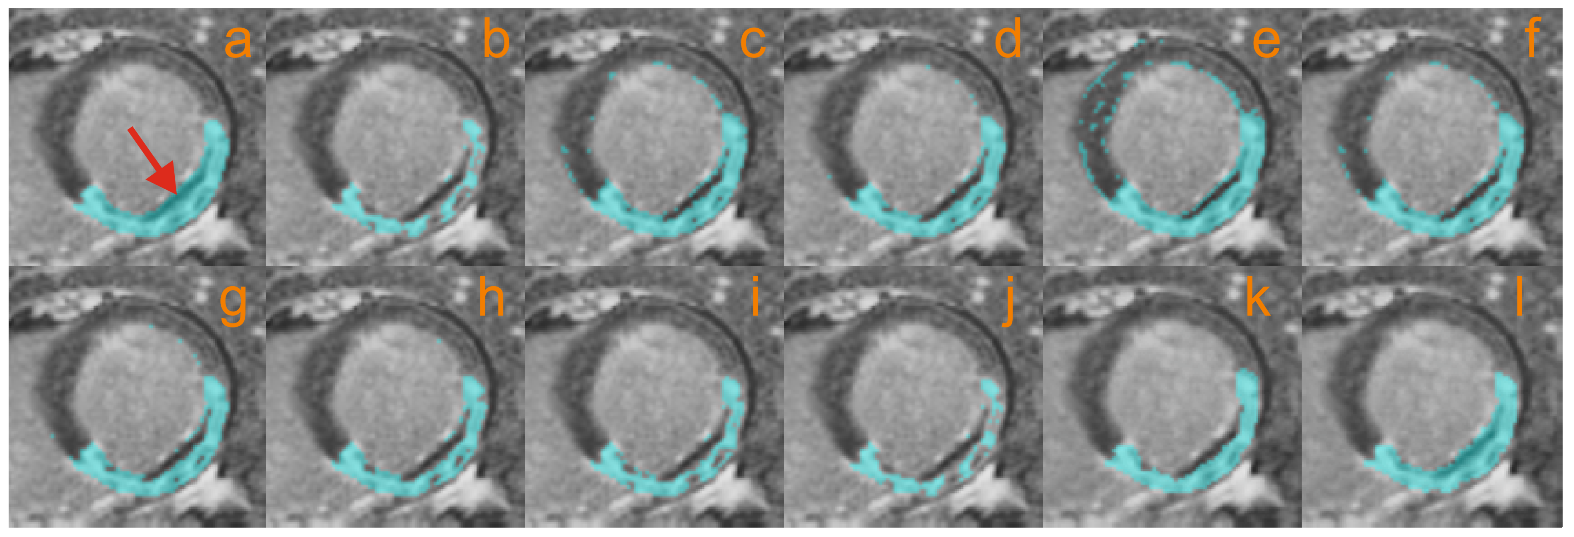

4.2.3. Microvascular Obstruction Inclusion